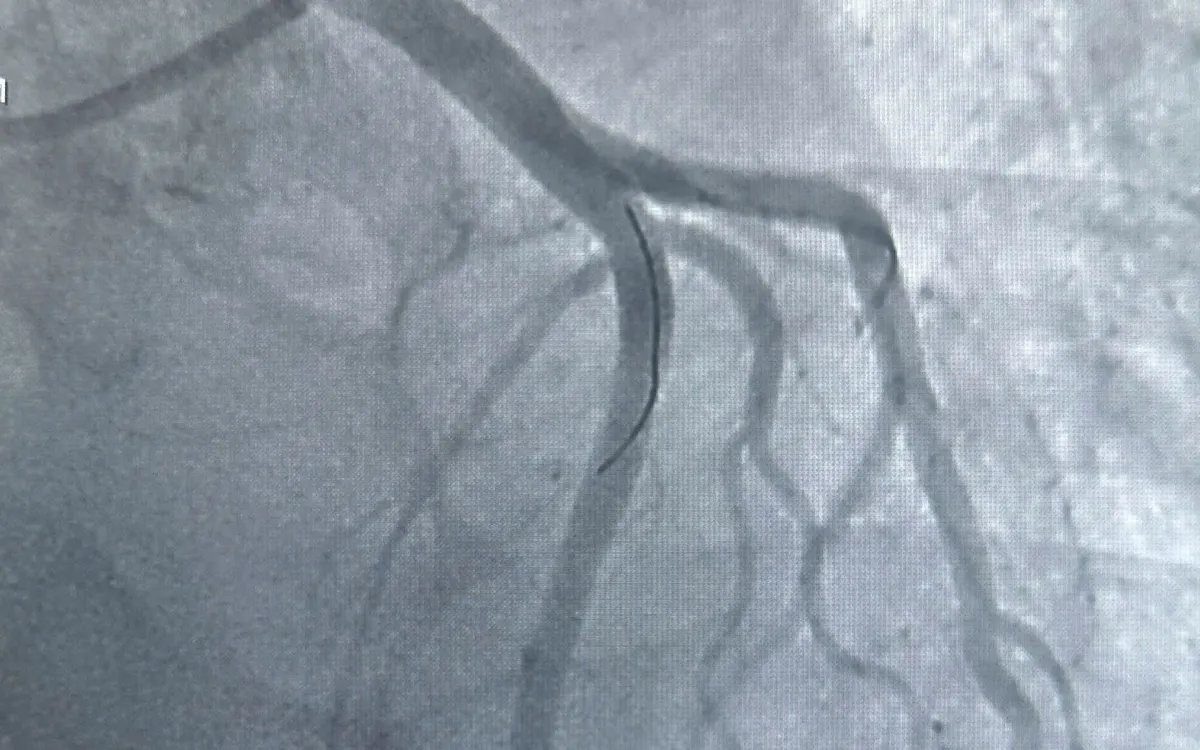

Bệnh nhân L.V.D. (46 tuổi) nhập viện trong tình trạng đau thắt ngực dữ dội, được chẩn đoán nhồi máu cơ tim cấp vùng trước. Bệnh nhân được đặt stent phủ thuốc mở thông đoạn tắc, sau can thiệp đã ổn định.

Một ca khác là bệnh nhân Đ.H.M. (55 tuổi) có nhiều bệnh nền, nhập viện muộn với nhồi máu cơ tim cấp vùng dưới. Kết quả DSA cho thấy mạch vành tổn thương cả ba nhánh, trong đó động mạch vành phải tắc hoàn toàn. Các bác sĩ đã đặt hai stent, cứu sống bệnh nhân trong tình huống nguy kịch.

Theo các chuyên gia, hệ thống chụp mạch số hóa xóa nền (DSA) giúp bác sĩ xác định chính xác vị trí tắc hẹp, từ đó can thiệp ngay tại chỗ, giảm biến chứng và rút ngắn thời gian điều trị. Bệnh viện Đa khoa Vĩnh Long hiện đã ứng dụng hiệu quả kỹ thuật này trong cấp cứu tim mạch, góp phần giảm tỷ lệ tử vong do nhồi máu cơ tim tại địa phương.